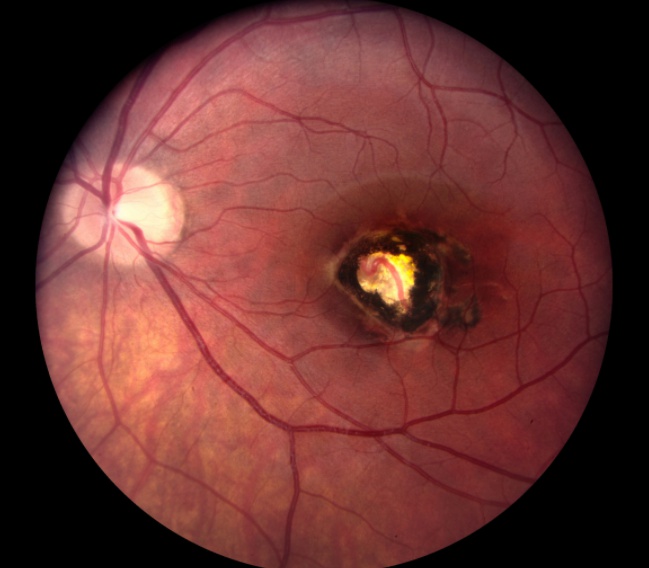

flash bulb looking like retina: Congenital Toxoplasmosis: Chorioretinitis